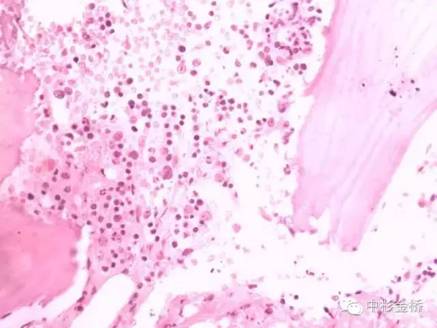

Rapidcal.Immuno脫鈣處理的骨髓標本,易于2?m連續(xù)完整切片,鏡下結(jié)構(gòu)清晰,細胞核與漿顏色鮮艷;常規(guī)硝酸脫鈣的骨髓標本,鏡下細胞核與漿顏色對比不明顯,染色質(zhì)不清晰。免疫組化實驗中,Rapidcal.Immuno脫鈣處理的骨髓標本,CD3、CD4、CD79a、CD20所標記的T細胞和B細胞定位準確,陽性表達強,背景清晰。常規(guī)硝酸脫鈣的骨髓標本,抗原部分丟失,標記物陽性結(jié)果表達較弱,背景有部分非特異性著色。

免疫組化CD79a好